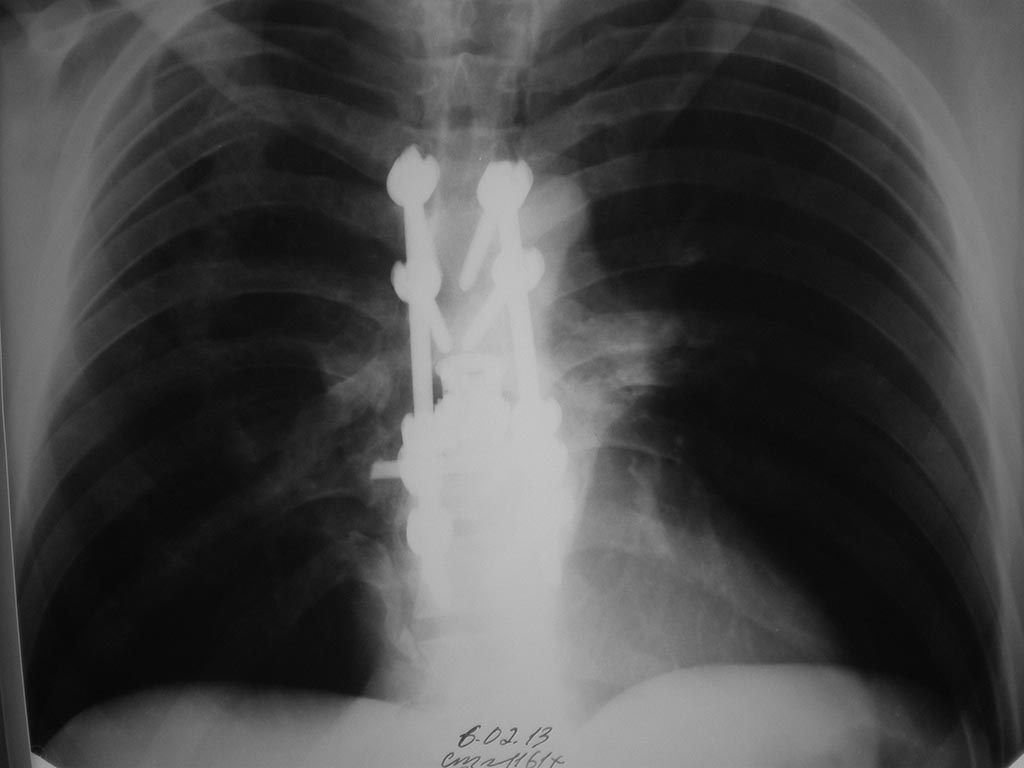

Re: Инфицированная рана области п/о рубца после ТПФ

Добрый вечер. Добавляю фото.